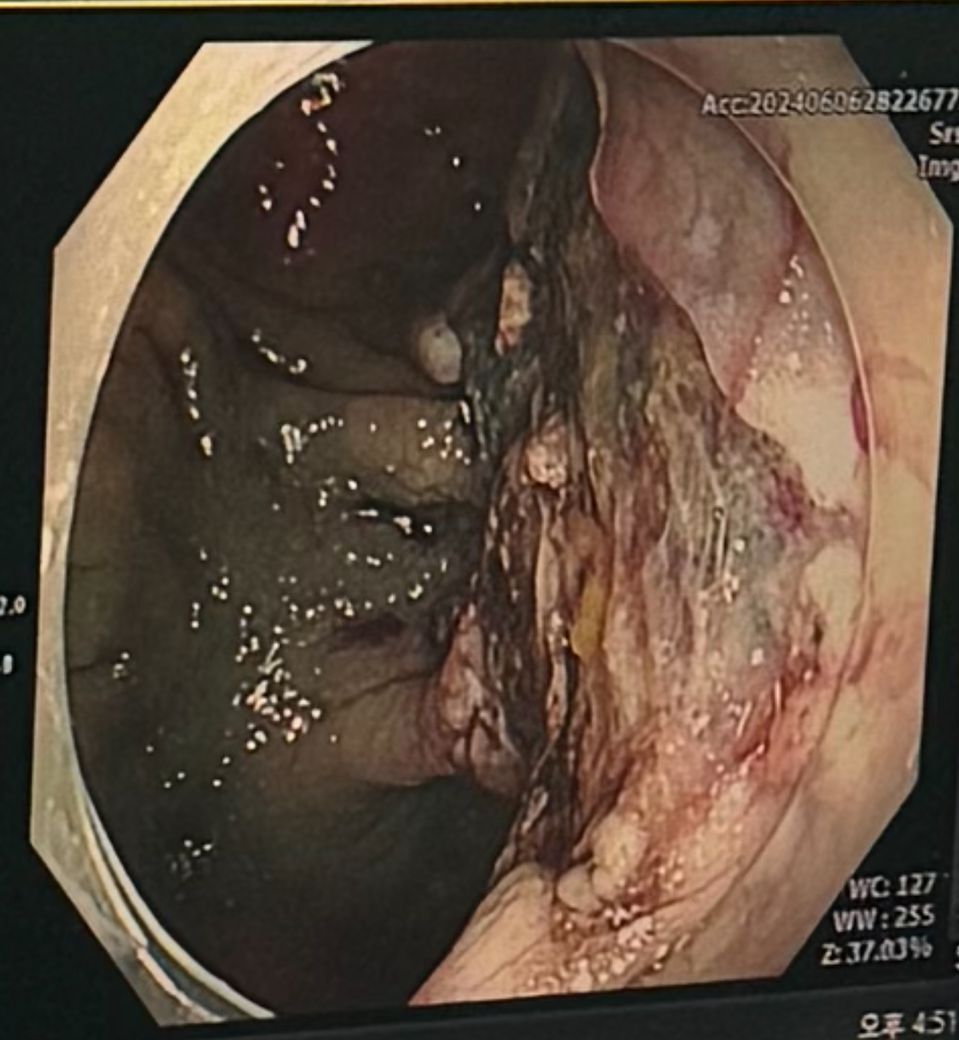

어머니께서 첫 번째 사진처럼 대장용종이 발견이 되셔서 중소형 대학병원에서 제거술을 하셨습니다. 처음 내시경때는 제거를 못하셨고 두번째 내시경에서도 깔끔하게 용종이 떠지지 않아서 전기 소작? 식으로 쉽게말해 지져서 용종을 제거했다고 하셨습니다. 제가 궁금한건 보통 깔끔하게 용종을 잡아서 떼어내지 않고 이렇게 지져서 치려하는 방식도 괜찮은 걸까요?? 시술하신 선생님을 탓하려고 하는게 아니고 이런식으로도 치료가 이루이지는지, 그리고 차후에 문제는 없을지 궁금합니다. 만일 대중적인 방법이 아니라면 병원을 조금 더 큰 곳으로 옮겨 보려고 합니다

• 1번 째 사진

올려주신 사진으로 미루어 측방발육종양의 가능성이 생각되며 크기가 커 일반적인 용종절제방법으로는 변연부를 깨끗하게 제거하기 어려운 병변으로 점막절제술이 필요합니다.

점막절제를 위해서는 전기 소작기를 이용하여 점막을 절제하게 되며 범위가 넓고 전기 통전으로 인한 장 천공과 같은 합병증의 가능성이 있으나 제거 후 특별한 합병증이 없었다면 큰 문제가 되진 않겠습니다.